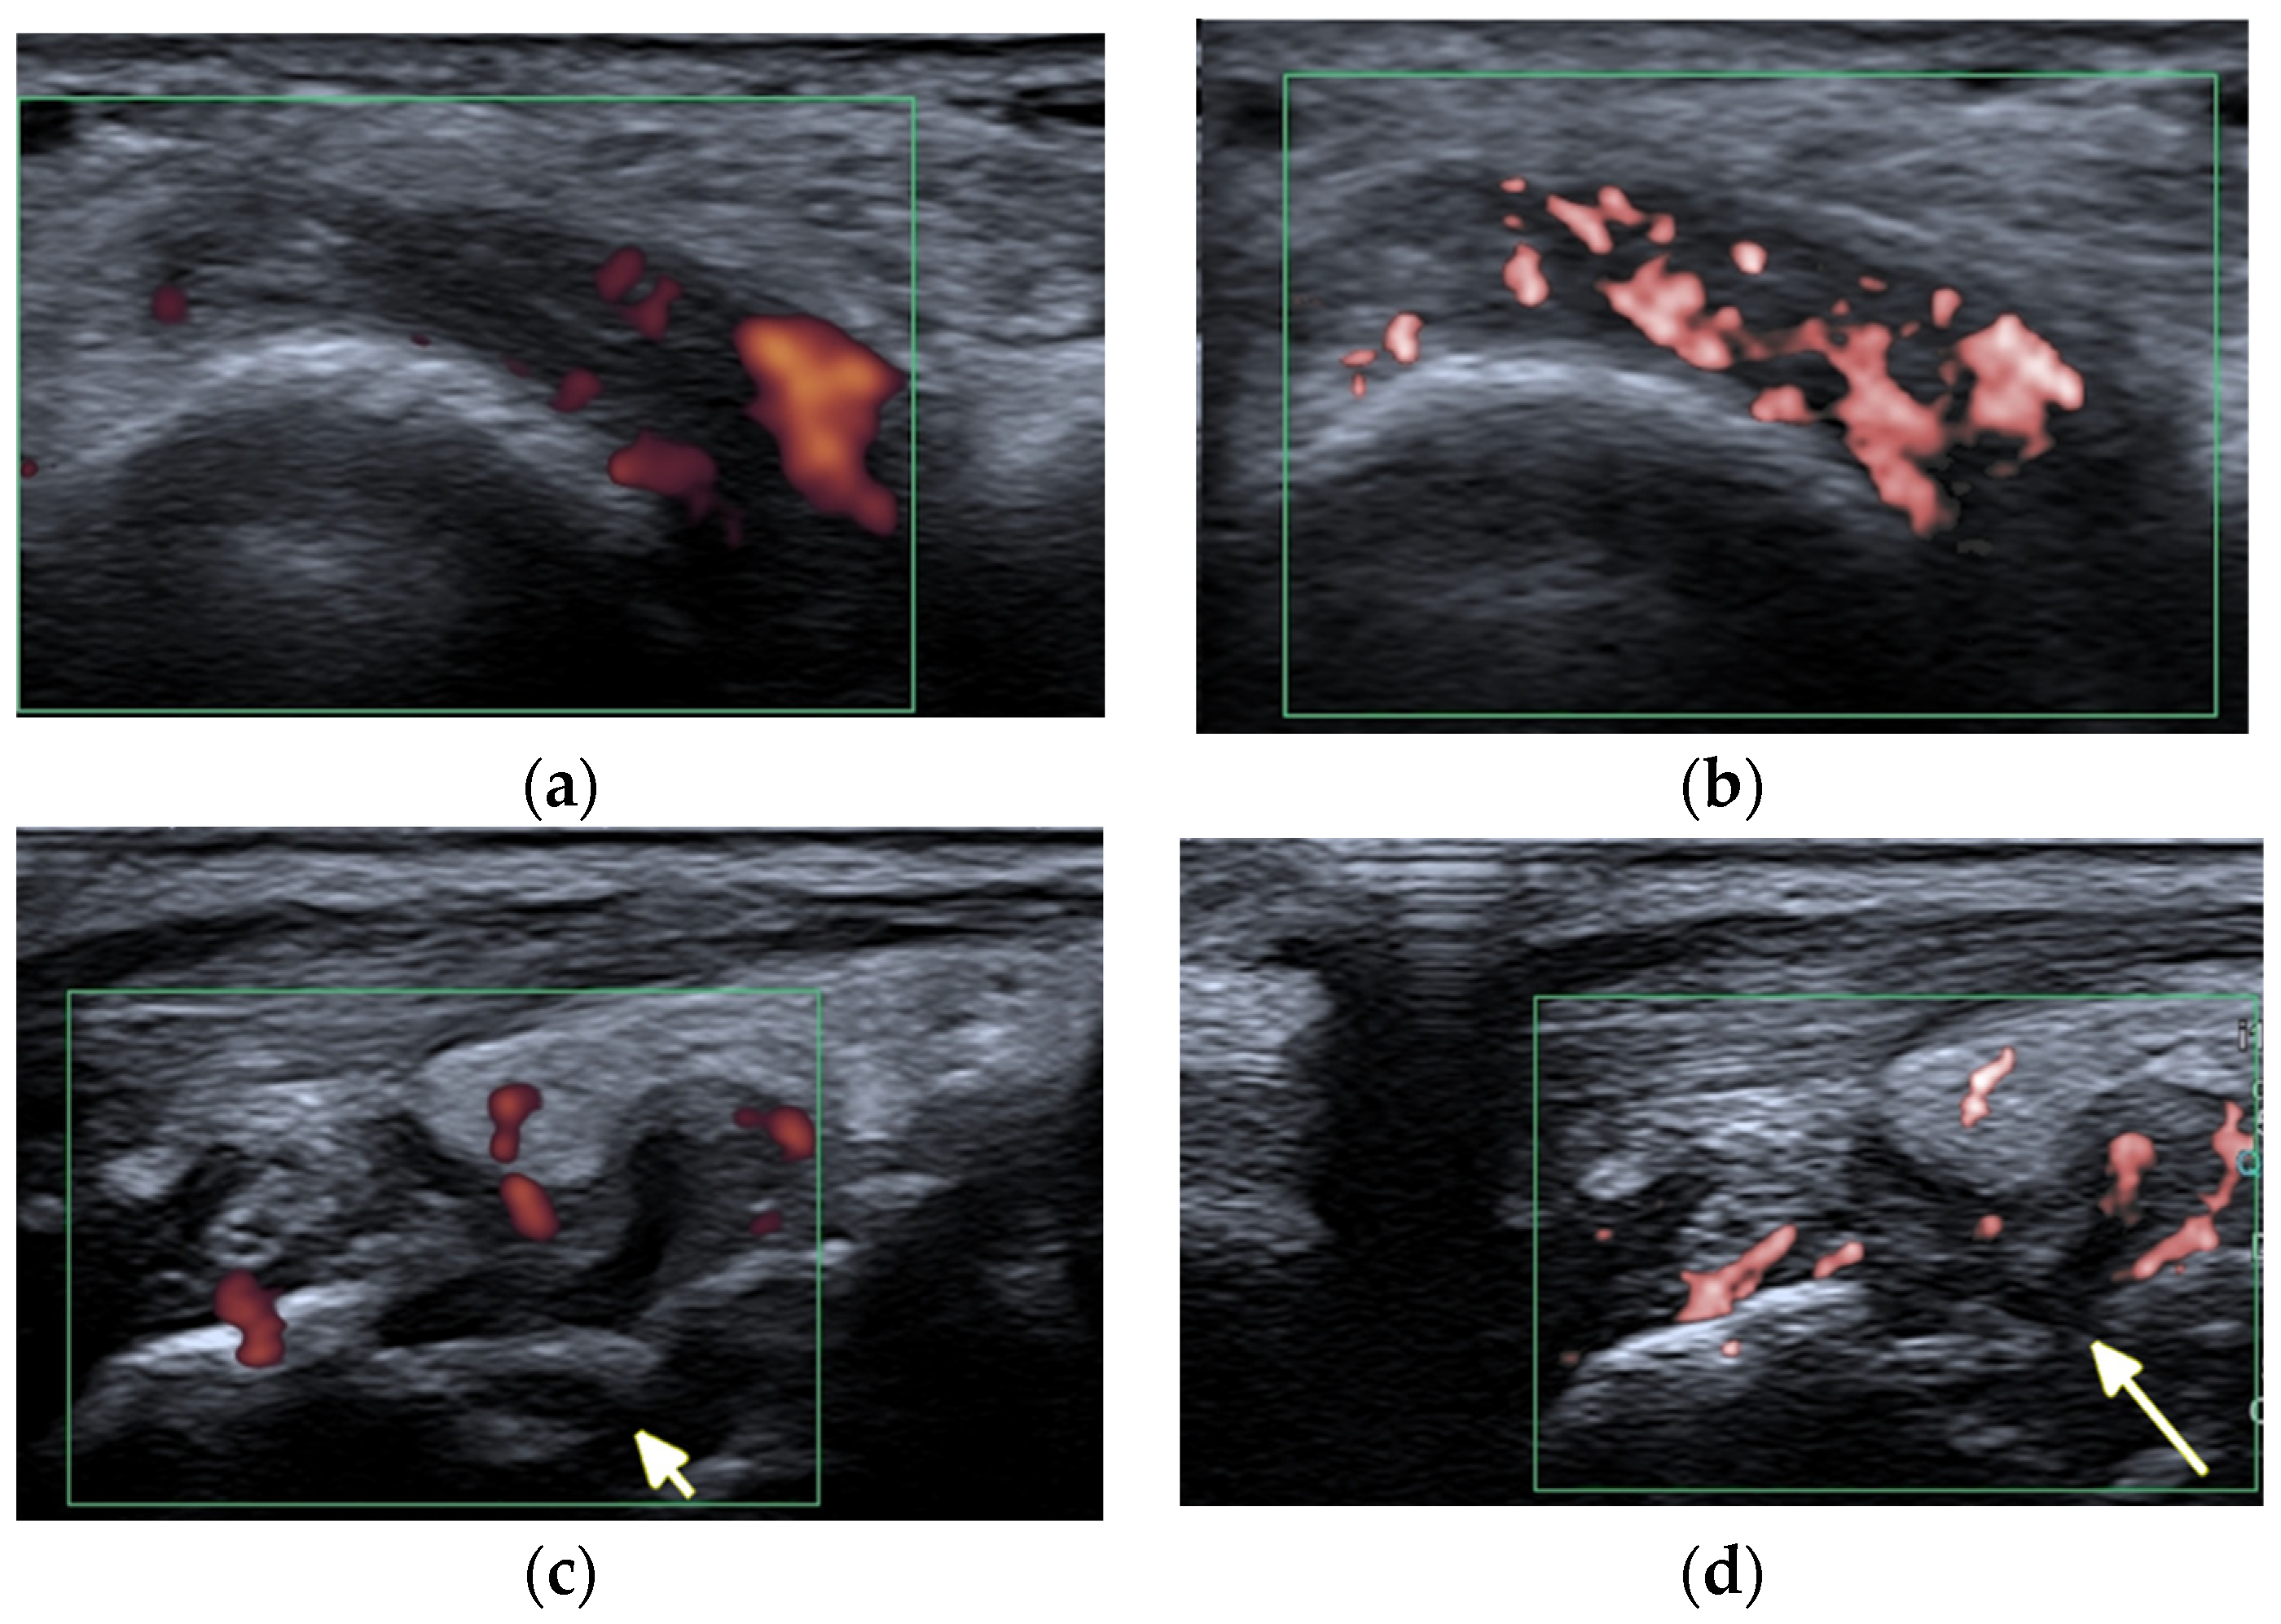

Figure 5.

A 57-year-old patient with systemic lupus erythematosus. (a) Short-axis power Doppler and (b) superb micro-vascular imaging (SMI) ultrasound (US) images of the distal radioulnar joint. (c) Long-axis power Doppler and (d) SMI US images at the dorsal aspect of the radiocarpal and midcarpal joints show joint effusions and hyperemia consistent with synovitis with more vessels seen with SMI (b,d). Note an intra-osseous cyst-like change (short arrow) and cortical erosion (long arrow in (d)) in the carpal bone related to rhupus syndrome.